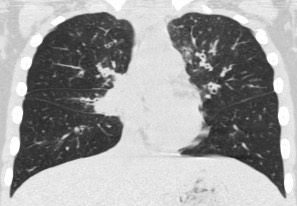

2963. Пациенту 12 лет с диагнозом «приобретенный иммунодефицит: общая вариабельная иммунная недостаточность», состояние после торакоскопической биопсии верхней доли правого легкого выполнена компьютерная томография, рентгенологическая картина соответствует